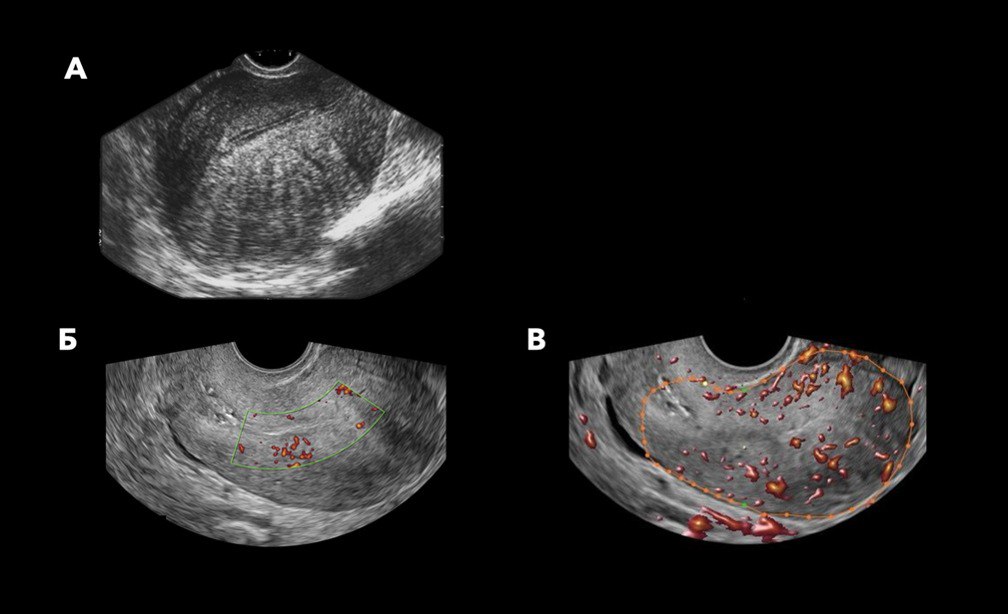

Гольмиевый лазер работает иначе — луч прицельно испаряет очаги эндометриоза. Процесс при этом контролируется с помощью ультразвукового сканера, что снижает риск повреждения сосудов и тканей.